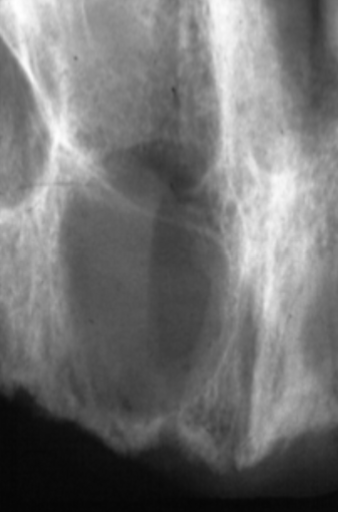

Describe the radiographic features of this Buccal Bifurcation Cyst?

Buccal Bifurcation of Molars

Roots Displaced Lingually

Occlusal Plane Inclined Buccally

Lingual Cusp Higher on BWs and PAs